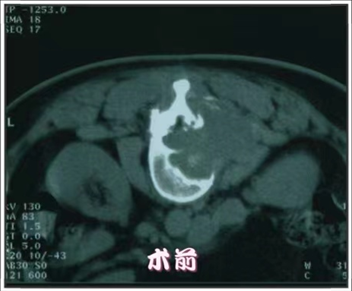

放射性粒子植入术

放射性粒子治疗是利用现代影像学技术将具有放射性核素直接插到肿瘤靶体积内或肿瘤周围,通过放射性核素持续释放射线对肿瘤细胞进行杀伤。